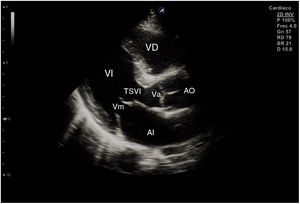

El plano paraesternal de eje largo se obtiene con la sonda sobre el segundo o el tercer espacio intercostal izquierdo, próxima al esternón y perpendicular a la piel, sobre una línea que une el hombro derecho con la cadera izquierda (fig. 2). La zona más próxima al transductor es la pared anterior del ventrículo derecho (VD), siendo también visibles la válvula mitral, la válvula aórtica (valva coronaria derecha y no coronaria), el ventrículo izquierdo (VI), la aurícula izquierda (AI), el tracto de salida del VI con la raíz aórtica, parte de la aorta ascendente y el pericardio. Si el corte es bueno, el septo interventricular anterior y la pared anterior de la aorta deben estar alineadas al mismo nivel y dispuestas de forma perpendicular al plano de estudio. La válvula mitral aparece en el centro de la imagen, de forma que su valva anterior se continúa con la pared posterior de la aorta. La aorta descendente puede verse también por detrás de la AI (fig. 3).

Para obtener los planos apicales la sonda se coloca sobre el latido cardiaco en el ápex, bajo la mamilla izquierda, a la altura del quinto espacio intercostal, con la marca dirigida a la izquierda del paciente y angulado en dirección al hombro derecho. Este plano, apical de 4 cámaras (fig. 8), muestra las 4 cavidades cardiacas y las válvulas auriculoventriculares vistas desde el ápex (fig. 9). En él, el plano del anillo tricuspídeo se sitúa más cerca del ápex que el mitral y el VD se ve más trabeculado. Es la vista de elección para medir la superficie de la AI, comparar el tamaño de ambos ventrículos y descartar la presencia de disfunción y/o dilatación ventricular. Angulando el transductor hacia anterior se obtiene el plano apical de 5 cámaras, que permite observar el tracto de salida del VI y valorar el flujo a través de la válvula aórtica (fig. 10); y al rotarlo 90° en sentido antihorario, el apical de 2 cámaras, que muestra las paredes anterior e inferior del VI (fig. 11).